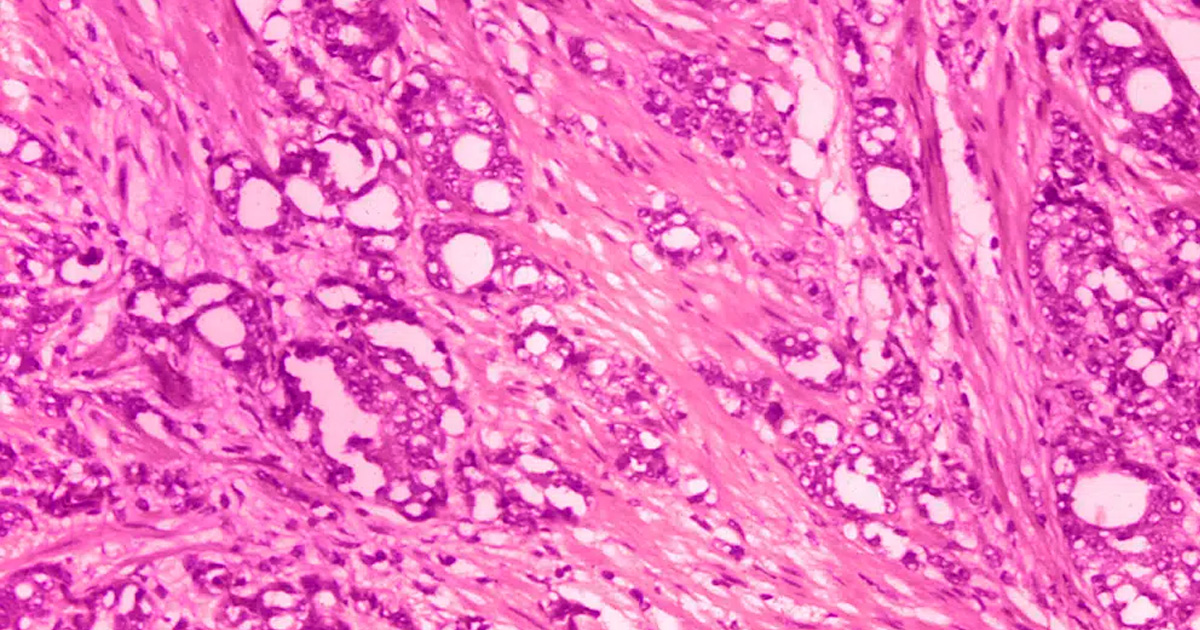

Los pacientes tenían localizado el cáncer en la próstata, una glándula del tamaño de una nuez que forma parte del sistema reproductivo.